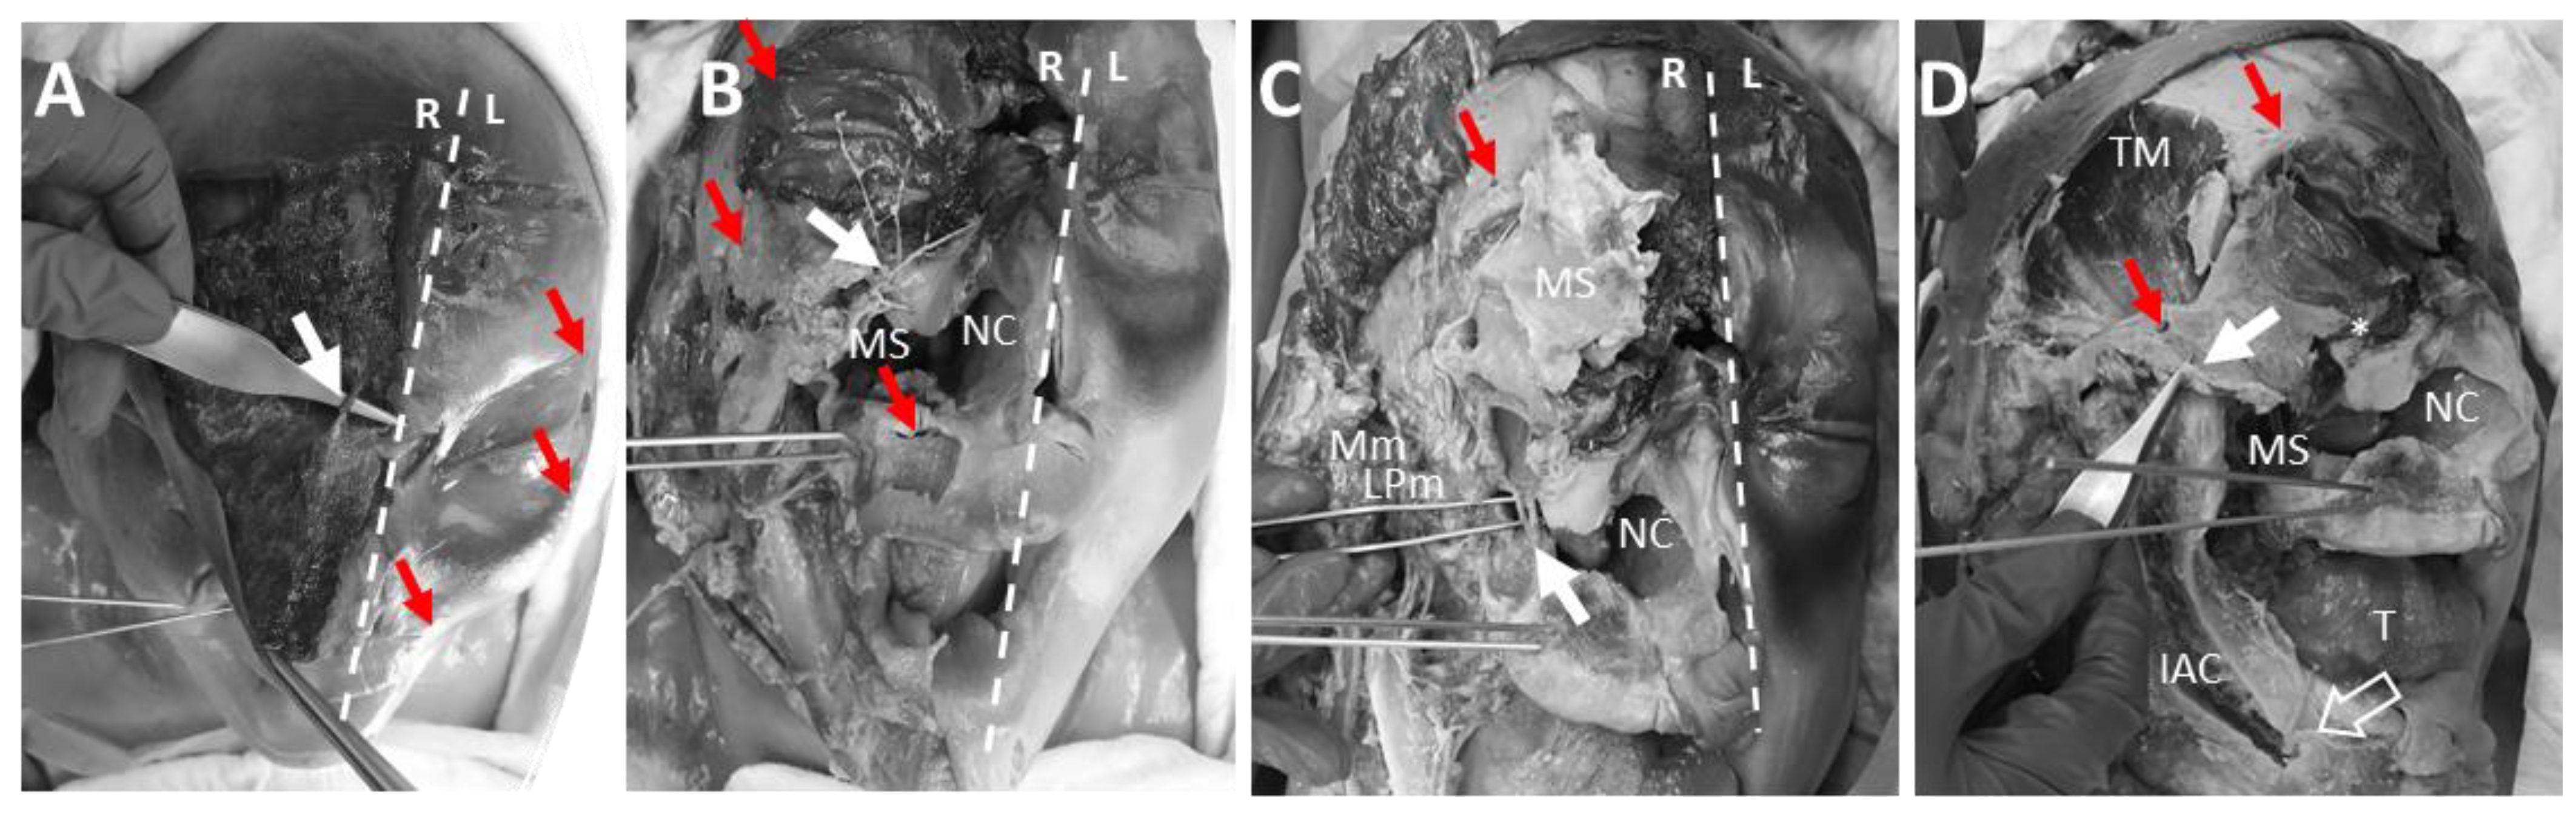

3.5. Anatomical Dissection of the Pin Insertion Areas and Description of Structures at Risk

4.5. Anatomical Dissection of the Pin Insertion Sites